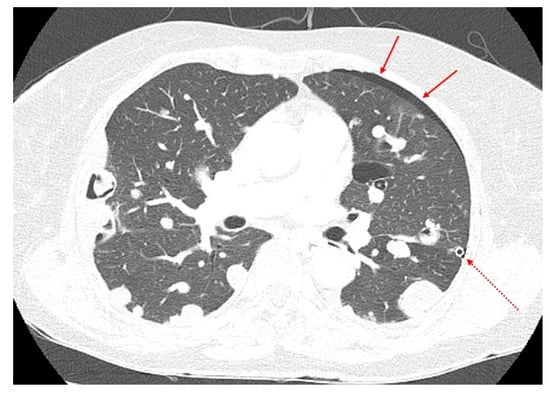

After initiating hormonal therapy, the size and number of lung masses decreased on subsequent chest CT, and bilateral pleural effusions disappeared completely. The size of the pelvic masses also decreased slightly but not to the extent observed in lung lesions. Although tumors were still unresectable, patient condition has been stable without significant toxicity from the treatment or recurrence of symptoms for 28 months (Figure 5). Her treatment is ongoing.

Figure 5.

Follow-up computed tomography examination. Follow-up chest computed tomography showed improved disease status (August 2021). (a) Coronal and (b) axial views.